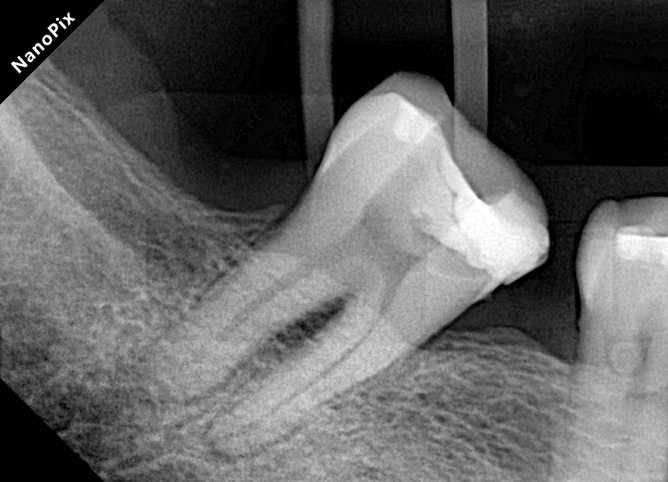

- Paciente con restauración desadaptada y sobrecarga mecánica severa por pérdida de piezas adyacentes.

- Imagen de RX asociada a periodontitis apical.

- Diagnóstico: Necrosis pulpar y periodontitis apical sintomática.

Diente: Pieza con anatomía afectada por necrosis pulpar + periodontitis apical sintomática.

La combinación de restauración desadaptada y pérdida de piezas adyacentes generó una sobrecarga mecánica importante, lo que exigía una instrumentación que permitiera un calibre apical amplio sin alterar la anatomía original ni debilitar excesivamente la estructura dentinaria.